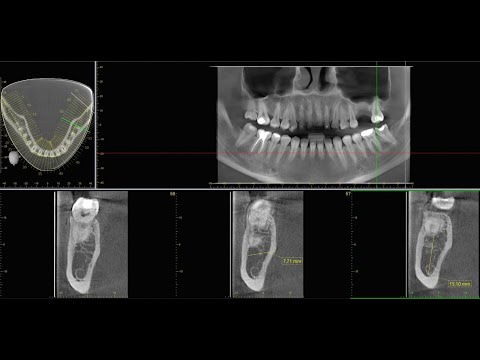

Morita X800 | Вводный инструктаж i-Dixel | i-Dixel қолданамасына кіріспе нұсқаулық

Данное видео показывает основные и базовые функции просмотрщика i-Dixel, для снимков оборудования Morita. Наш сайт:

3D Dental — ведущий диагностический центр Казахстане. Мы специализируемся на панорамных, ТРГ и 3D снимках. Наш центр оснащен современным и безопасным оборудованием, а именно – японским аппаратом Morita Veraview 3D X800. Благодаря этому достигается высокая точность изображений и диагностики, что довольно важно для назначения результативного курса лечения. Morita Veraview 3D X800 позволяет провести точную диагностику зубочелюстной системы, височно-нижнечелюстного сустава, костей лицевого черепа и пазух.